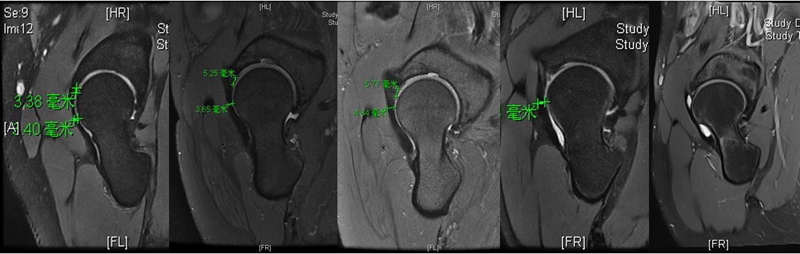

‌‌‌‌前关节囊除了进行X线指标的测量之外,我们尤其关注了厚度,测量方法选择在斜矢状位上,在整个前关节囊的‌‌中段进行了厚度的测量。见图9C中红色线段部位。

术前磁共振测量的案例

除厚度测量之外,也借助半月板的信号分级对前关节囊进行了内部信号分级。临床分为0~4级,‌正常表现是0级,出现点状信号为1级,出现线状信号为2级,出现断裂或者明显的贯通样分层为3级。‌‌

对这些测量数据进行统计学分析后发现DDH组的‌厚度均值是3.2,BDDH组是4.5,FAI组是4.7。统计学意义上来讲DDH组和BDDH组是有差异的,但是BDDH组和FAI组两者是没有差异的。‌‌但是在关节囊内信号分级上,‌‌‌这‌‌每两组之间都是有差异的。‌‌这也说明‌从厚度上来讲,DDH病人会导致前关节囊变薄,但是BDDH病人虽然没有观察到厚度的变化,但是‌‌也已经出现了囊内信号退变性的表现,我们称之为关节‌囊内部的水肿或者是分层表现。

通过对于关节囊厚度和关节囊信号的测量,是否存在一个能够帮我们区分哪些患者倾向于稳定,哪些患者倾向于不稳定这样的一个截断值?我们‌‌通过一个病例设定‌‌截断值大概在4mm,‌通过观察发现,‌‌在<4mm的病例主要集中在DDH,而基本上所有BDDH和FAI病人的关节囊厚度都是>4mm的。所以我们提出一个‌‌预先的、简洁的记忆标准,即4mm可能作为判断关节囊是否比较薄,启示关节囊不稳定的一个数值。